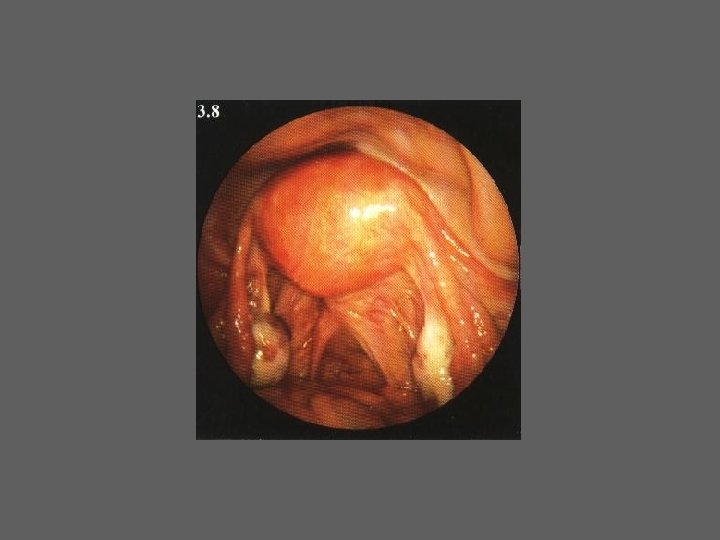

HISTEROSCOPIA - INDICAÇÕES Todas a situações em que se julgue vantajosa uma visualização completa da cavidade uterina, em particular: – Metrorragias – Dismenorreia adquirida – Infertilidade – Abortamentos de repetição e parto pré-termo – HSG anormal – DIU “perdido” – GIFT e ZIFT – Tratamento cirúrgico da patologia intracavitária: ● pólipos, miomas, septos, sinéquias, recessões endometriais ● baixos custos, reduzida morbilidade